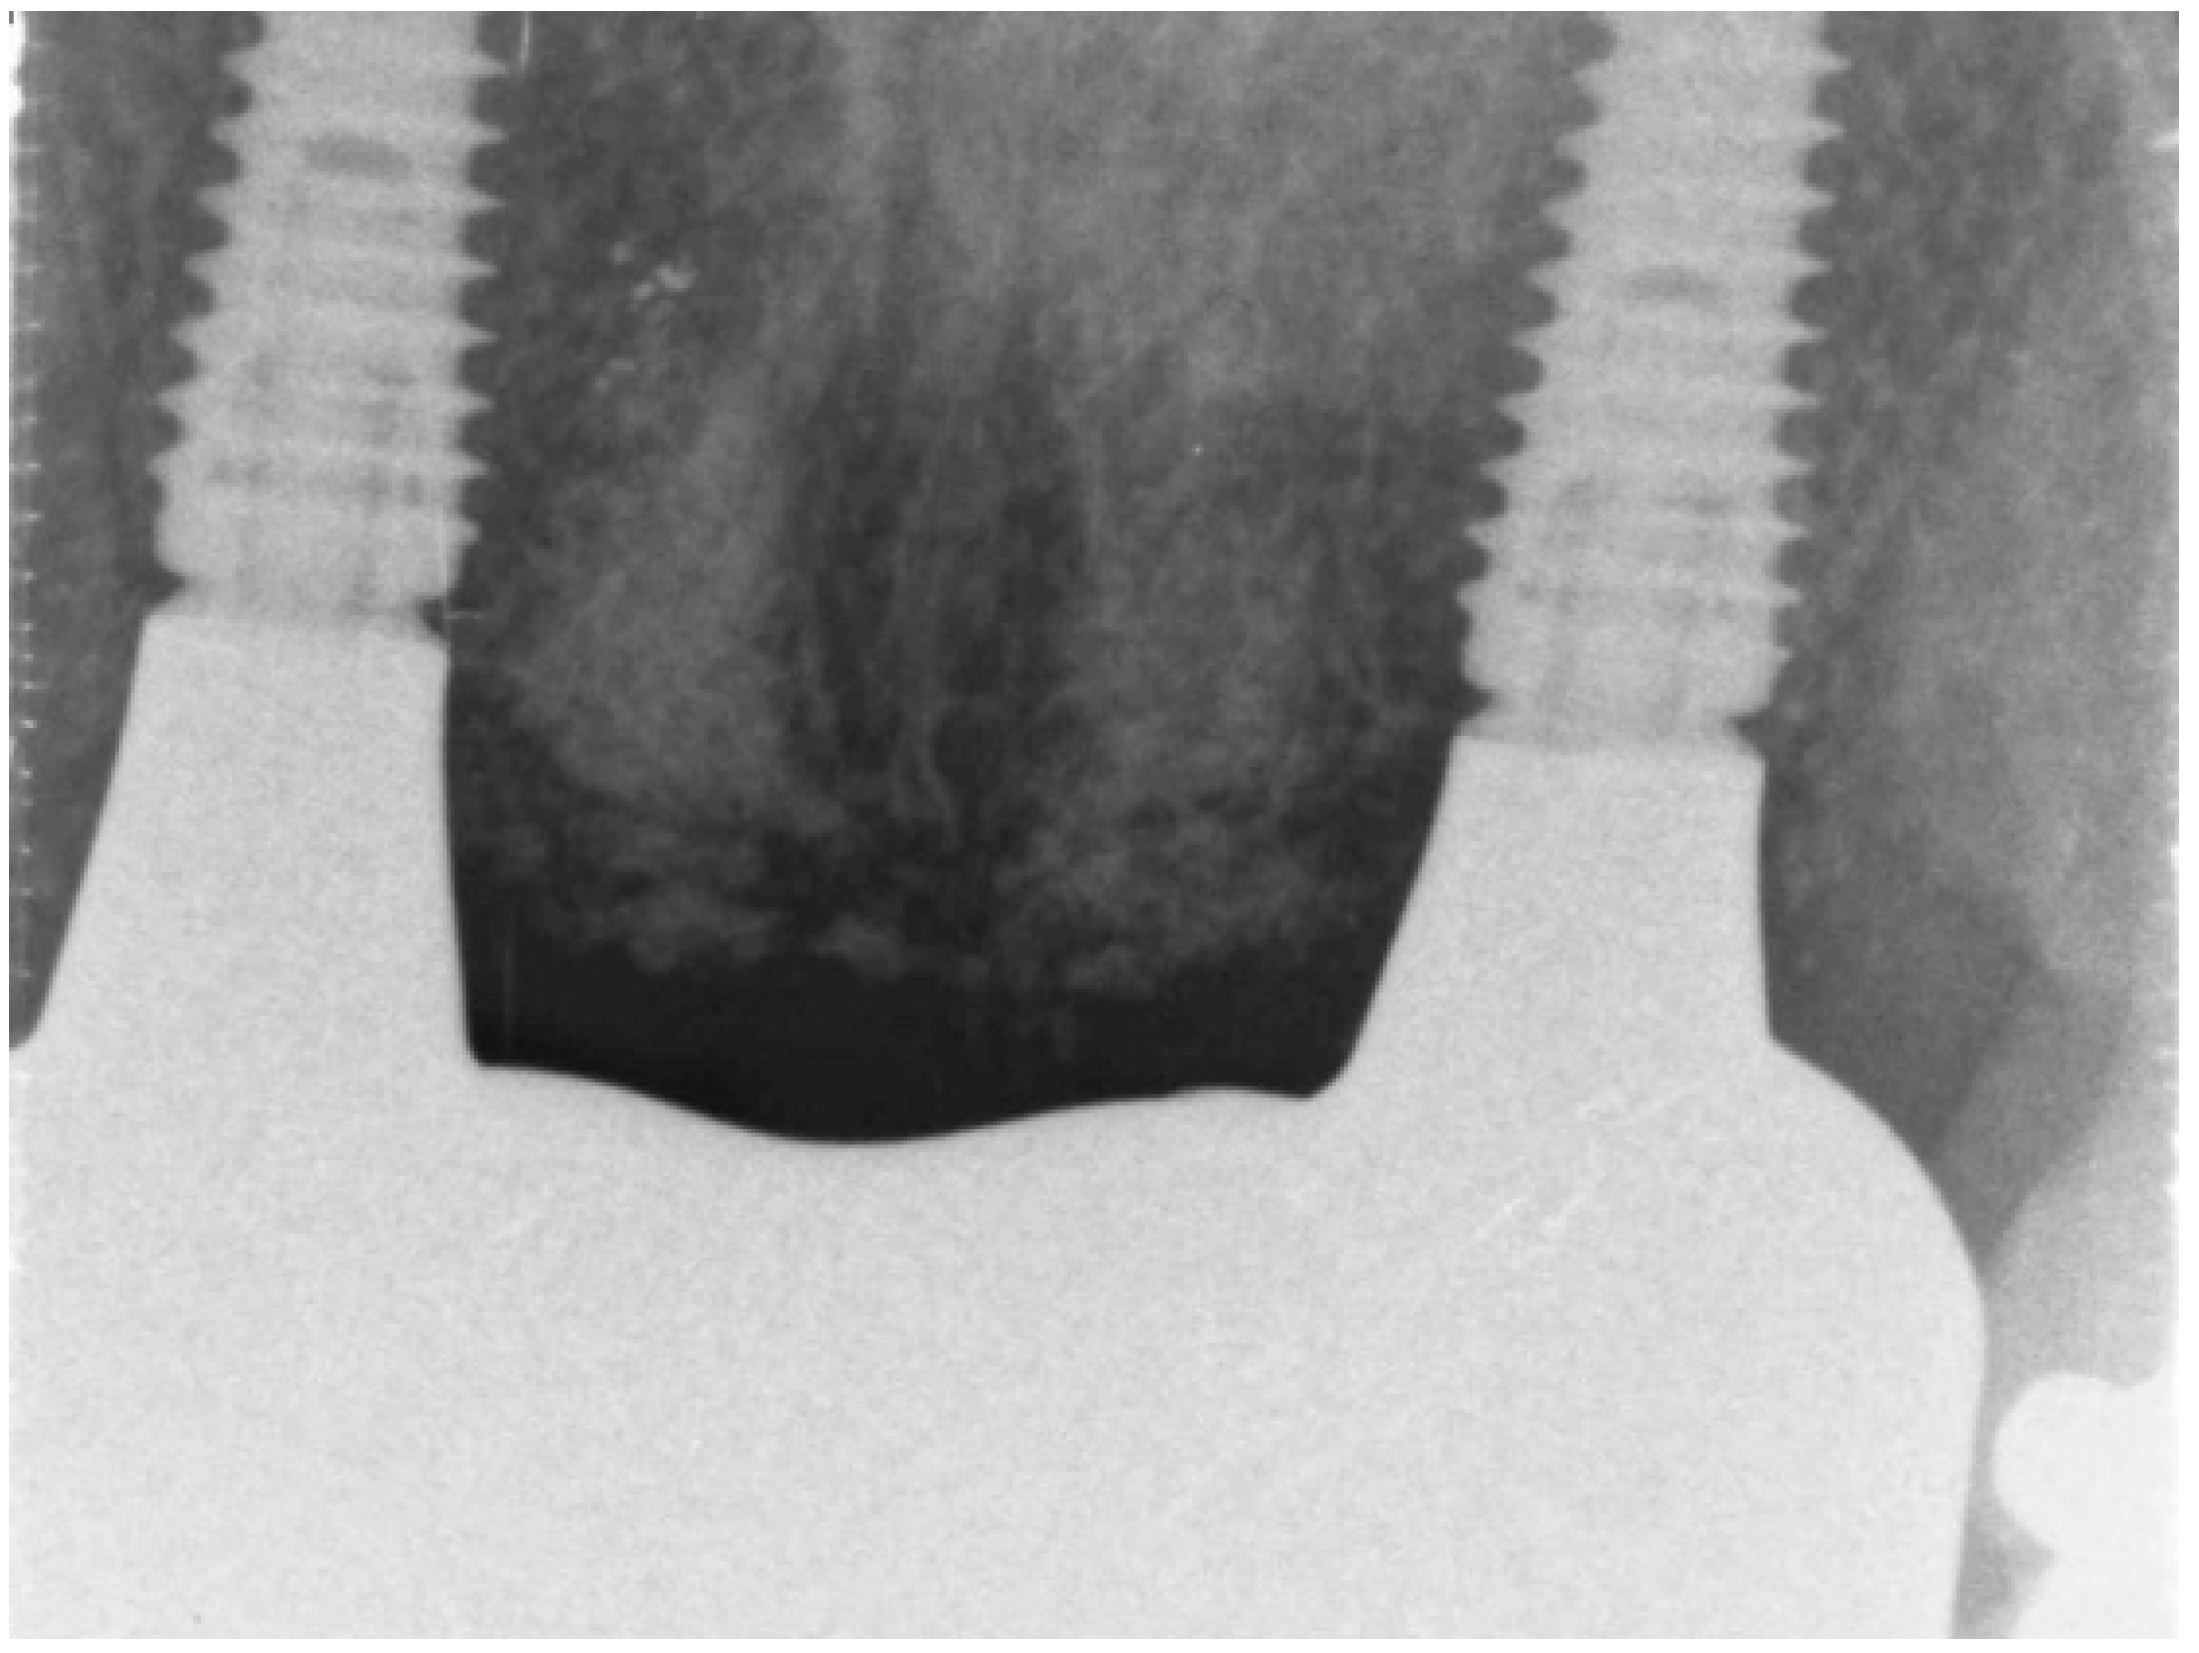

3.2. Case Study 2

| Case 2 implant 1 | open SA | Full contour | excellent | high | D2-4 | None | 9 weeks | 7 weeks | No crestal bone loss |

| Case 2 implant 2 | open SA | Full contour | excellent | high | D2-5 | None | 10 weeks | 8 weeks | No crestal bone loss |